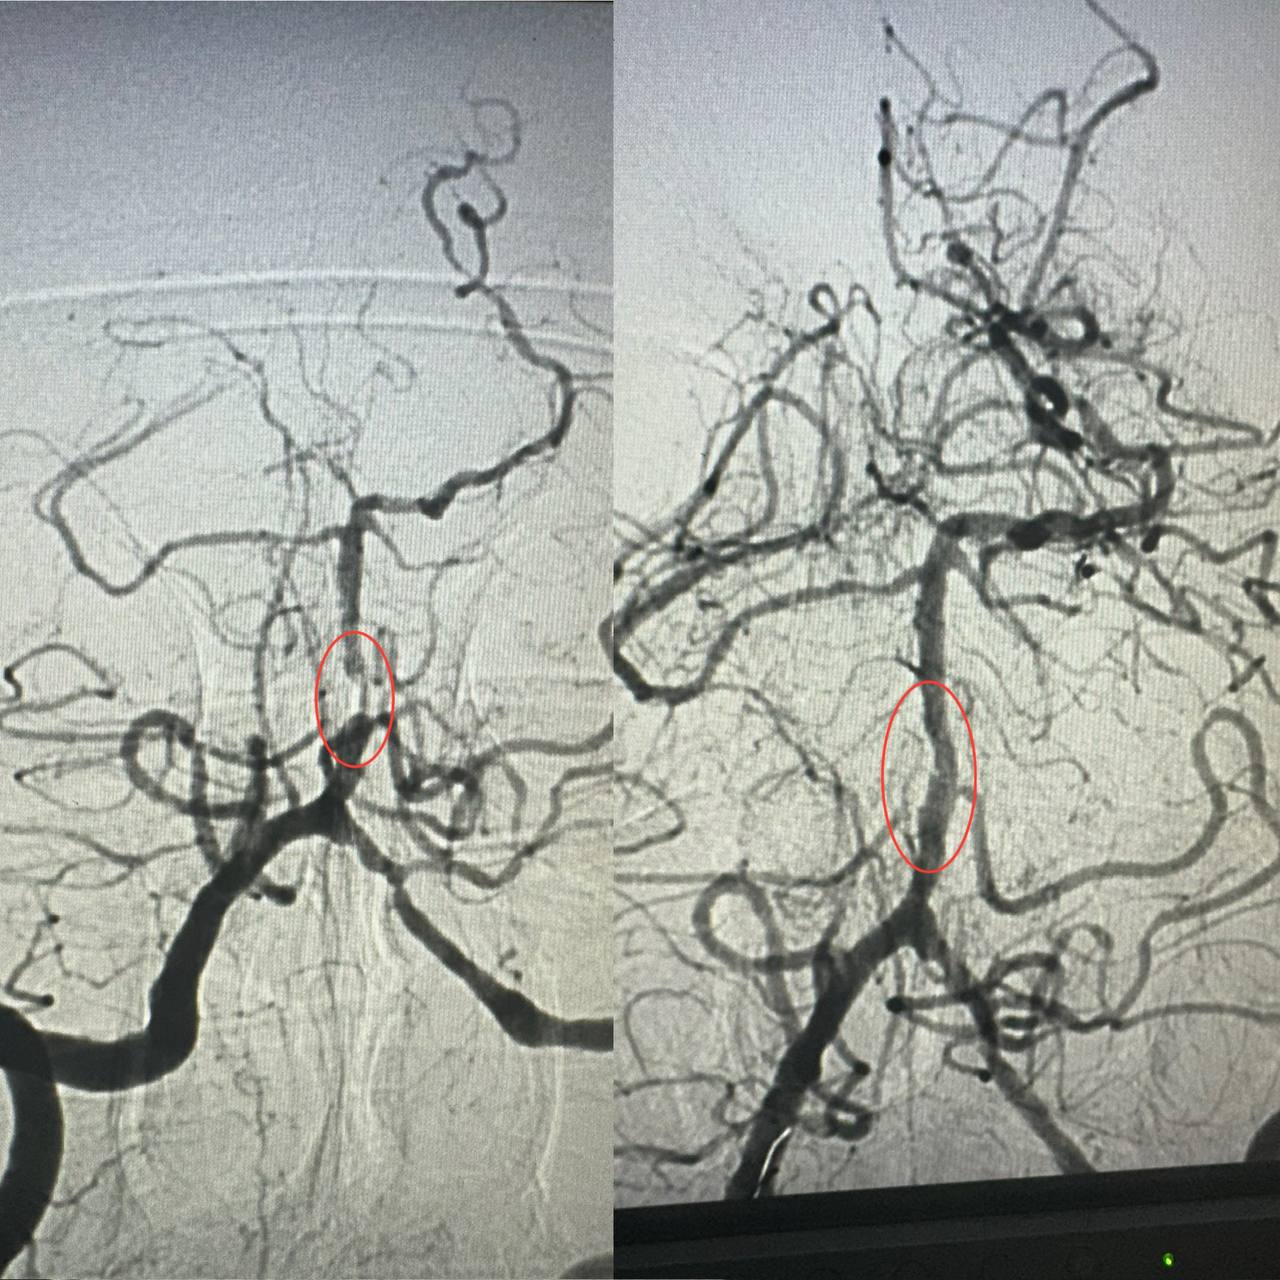

По словам заведующего рентгенэндоваскулярным блоком больницы Александра Скрипки, речь шла о крайне опасном поражении — инсульте стволовой части мозга. Базилярная артерия была почти полностью заблокирована атеросклеротической бляшкой, что создавало серьезную угрозу жизни.

Медики приняли решение провести ангиопластику пораженной артерии. Хотя больница имеет опыт такого вмешательства в кардиологии при атеросклерозе коронарных сосудов, но применение методики к мозговым артериям является новаторским подходом для украинской медицины.